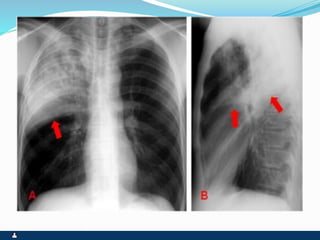

BRONQUIECTASIA

 DILATAÇÃO BRÔNQUICA IRREVERSÍVEL POR

DESTRUIÇÃO DAS ESTRUTURAS ANATÔMICAS

QUE FORMAM A PAREDE

 PÓS-INFECÇÃO (PNEUMONIA)

 PÓS-OBSTRUÇÃO ( CORPO ESTRANHO, ROLHAS

DE SECREÇÃO, TUMORES BRÔNQUICOS,

CONGÊNITA)

SINTOMAS SINAIS

 FACIES DE DOENÇA CRÔNICA

 INFECÇÃO DE REPETIÇÃO

 FEBRE OU FEBRÍCULA SEM

CAUSA APARENTE

 TOSSE PRODUTIVA CRÔNICA

 BRONCORRÉIA E DRENAGEM

POSTURAL

 HEMOPTÓICOS OU

HEMOPTISE

 VÔMICA EVENTUAL

 ESTADO GERAL NORMAL OU

EMAGRECIMENTO

 CIANOSE COM

HIPOCRATISMO DIGITAL

 EXPANSIBILIDADE REDUZIDA

 FTV REDUZIDO, NORMAL OU

AUMENTADO

 MV REDUZIDO

 RONCOS E SIBILOS

 ESTERTORES BRÔNQUICOS E

ALVEOLARES